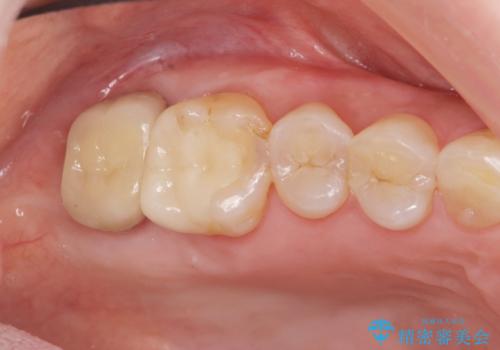

- 30万円(仮歯・ファイバーコア・ジルコニアクラウン・歯周外科・セラミックインレー)費用は治療当時の料金となります